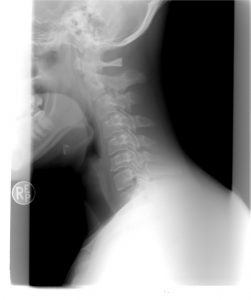

Proste ćwiczenia, które zmniejszają napięcie i ból w odcinku szyjnym kręgosłupa

Wiele osób cierpi dziś z powodu bólu szyi i karku. Jest to doskonałe ćwiczenie, które może zmniejszyć napięcie i ból. Odczujesz szybką ulgę i zmniejszenie napięcia.